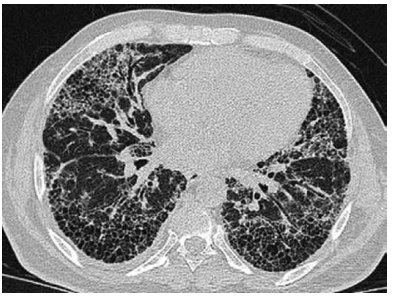

Um homem de 57 anos de idade, tabagista com

35 anos/maço, apresentou quadro de dispneia durante

realização de esforços, com evolução progressiva nos

últimos meses. A tomografia computadorizada de tórax

está disponibilizada a seguir

Com base nessa situação hipotética, assinale a alternativa que apresenta o diagnóstico, o resultado da espirometria e do exame físico, respectivamente,